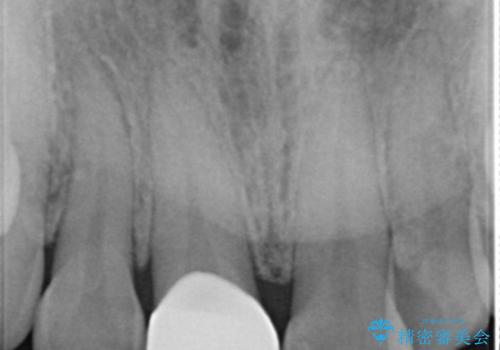

- 上顎前歯の歯冠部が破折した患者様です。神経にまでは到達していなかったので精密根管治療は行わず、審美性を考慮し、オールセラミッククラウンでの治療を選択しました。

歯ぎしりのある患者様なので、就寝時にマウスピースを着用するようにお伝えしています。